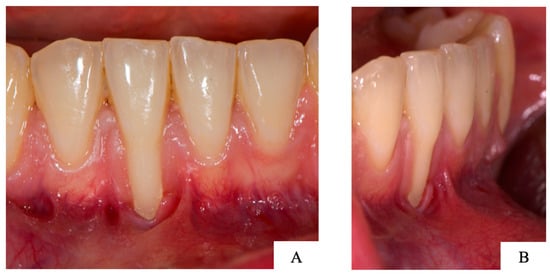

2.5. Case Report: Clinical Analysis

3.3. Case Report: Clinical Analysis